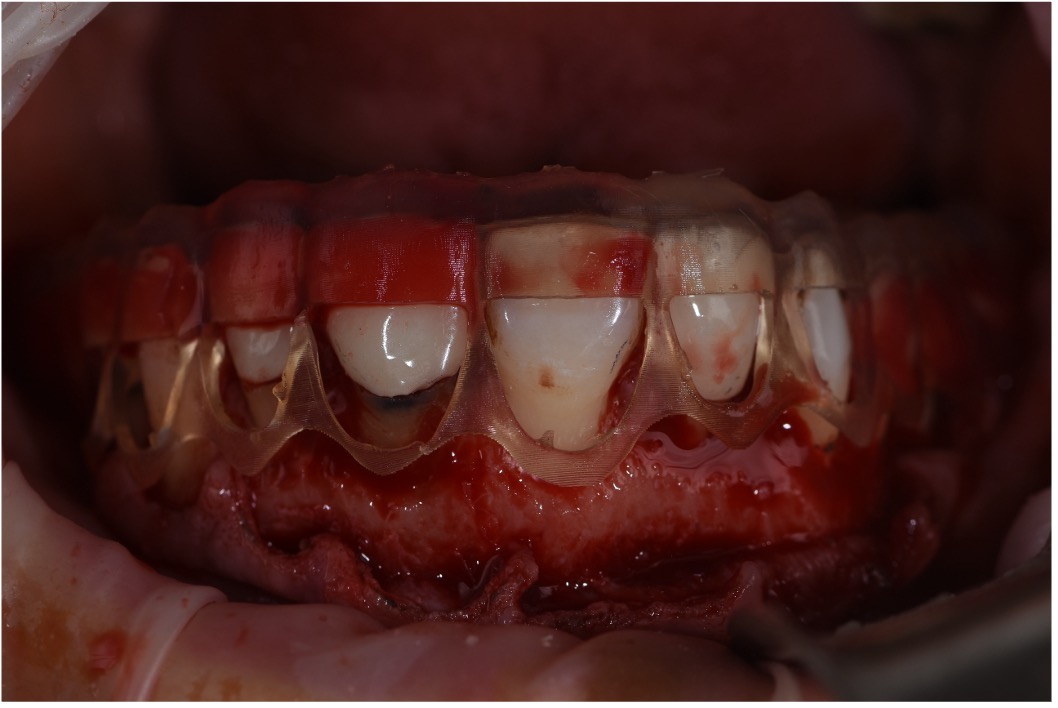

involving both surgical and restorative phases. The periodontist performed gingival recontouring to reduce the gummy smile and define ideal gingival margins. Diagnostic wax-ups and CBCT scans were essential tools in guiding this stage, helping to visualize bone levels, tooth proportions, and soft tissue behavior. A surgical guide was fabricated in this stage to showcase the amount of gum that will be removed to reach the digital smile design phase

architecture. These restorations were fabricated with high precision, ensuring excellent fit, esthetics, and durability. The bonding procedure was carried out with attention to Figure 19: 3D Printed Surgical Guide Try In Figure 20: Close Up Difference between 3D Printed Mockup and Initial Teeth Figure 21: During digital crown lengthening Figure 22: Post Op Intraoral Picture detail, followed by polishing to achieve a natural and vibrant finish. The completed smile